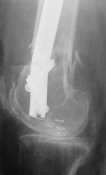

Attached are few examples from our Hospital:

B. Fixation loosening: distal cutting of the nail, non-unions do happen (cases attached).

Locking Plating has more distal screws than any nail, fixed angles and provides much better fixation, especially in osteoporotic bone.